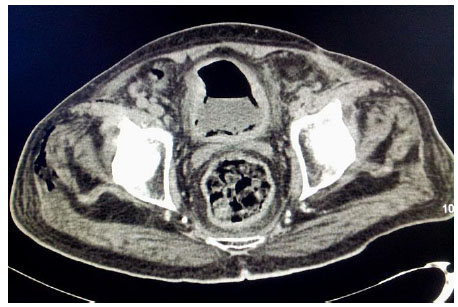

An elderly gentleman, aged 83 years, with diabetic end-stage renal disease, who was on maintenance haemodialysis, complained of severe pain in both the thighs when he came for his scheduled dialysis. He reported that the pain was severe, and he was unable to walk and attend his activities of daily living (ADL). He presented no history of fall or fever. He had been receiving twice weekly haemodialysis through left brachiocephalic arteriovenous fistula for the last one year. His regular medications included human premixed insulin 8 units daily, sustained release of Nifedipine 20 mg twice daily along with tab calcium carbonate and vitamin supplements.He was ambulatory and required no assistance for ADL earlier. His diabetic status and blood pressure were fairly under control till this event. Examination revealed no inflammatory signs. There was no evidence of fracture clinically and he was prescribed some anti-inflammatory drugs. He returned for his scheduled dialysis again after three days complaining of persistent pain. He appeared sick, but was stable hemodynamically. He was in severe agony with his slightest movement.There was local tenderness but no other inflammatory signs. He could complete haemodialysis without event and refused further investigations. He returned for the scheduled dialysis again after three days. This time, he reported fever with chills for two days prior to the hospital visit and presented in a moribund state. He was febrile and had excruciating pain in both the thighs. The slightest movement of lower limbs caused him severe pain. His vitals included BP of 180/110 mm of Hg, pulse rate of 130 beats/min and respiratory rate of 24 cycles per minute. He was conscious and fully oriented. He had severe tenderness in the lower abdomen and in both the thighs with no other inflammatory signs.Laboratory investigations revealed haemoglobin 11.1gm/dl, total leucocyte count 24300 cells/cu mm with polymorphonuclear neutrophil predominance and a platelet count of 213000 cells /cu mm. Random blood sugar was 501 mg/dl. Serum creatinine, calcium and phosphorus were 6.4, 9.8 and 5 mg/dl, respectively. He had normal serum electrolyte and uric acid. ABG revealed metabolic acidosis with a pH of 7.21 and serum bicarbonate being 11.2 mmol/l. Liver function test was normal except serum albumin of 3.0 g/dl. Urine was negative for ketones but microscopic examination showed 20-25 pus cells and red blood cells. Urine and blood culture both grew Escherichia coli. His chest X ray was normal. Ultrasound examination of the abdomen showed the presence of gas in the bladder and due to disproportionate symptoms, non-contrast CT scan abdomen was ordered. The CT scan revealed extensive mottled air pockets in the muscles of bilateral upper thigh, predominantly involving adductor compartments, right more than left Fig. (1). There was thickening of the urinary bladder wall with perivesical fat stranding and intramural as well as intraluminal air consistent with emphysematous cystitis Fig. (2). Mild left emphysematous pyelonephritis was also noted Fig. (3). He was treated with IV meropenem and Levofloxacin. Foley’s catheter was inserted for bladder drainage. Insulin infusion was started. However, he weakened quickly, became hypotensive and disoriented. Following this, haemodialysis was intensified, so he was treated with inotropic infusions and other supportive measures.The patient’s family refused surgical options.He succumbed 4 days after admission.